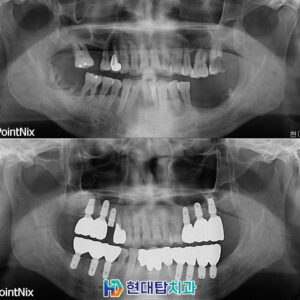

*모든 증례 사진은 의료법 제23조, 제 56조에 의거하여 환자분의 동의 하에 업로드가 진행되었습니다.

*치료 사진은 모두 본원에서 치료한 환자분의 사진입니다.

*치료 사진은 모두 동일인의 사진이며, 동일조건에서 촬영하였습니다.

*개인의 차이에 따라 시술 및 수술 후 부작용이 발생할 수 있으며, 의료진과 충분한 상담을 받으시기 바랍니다.